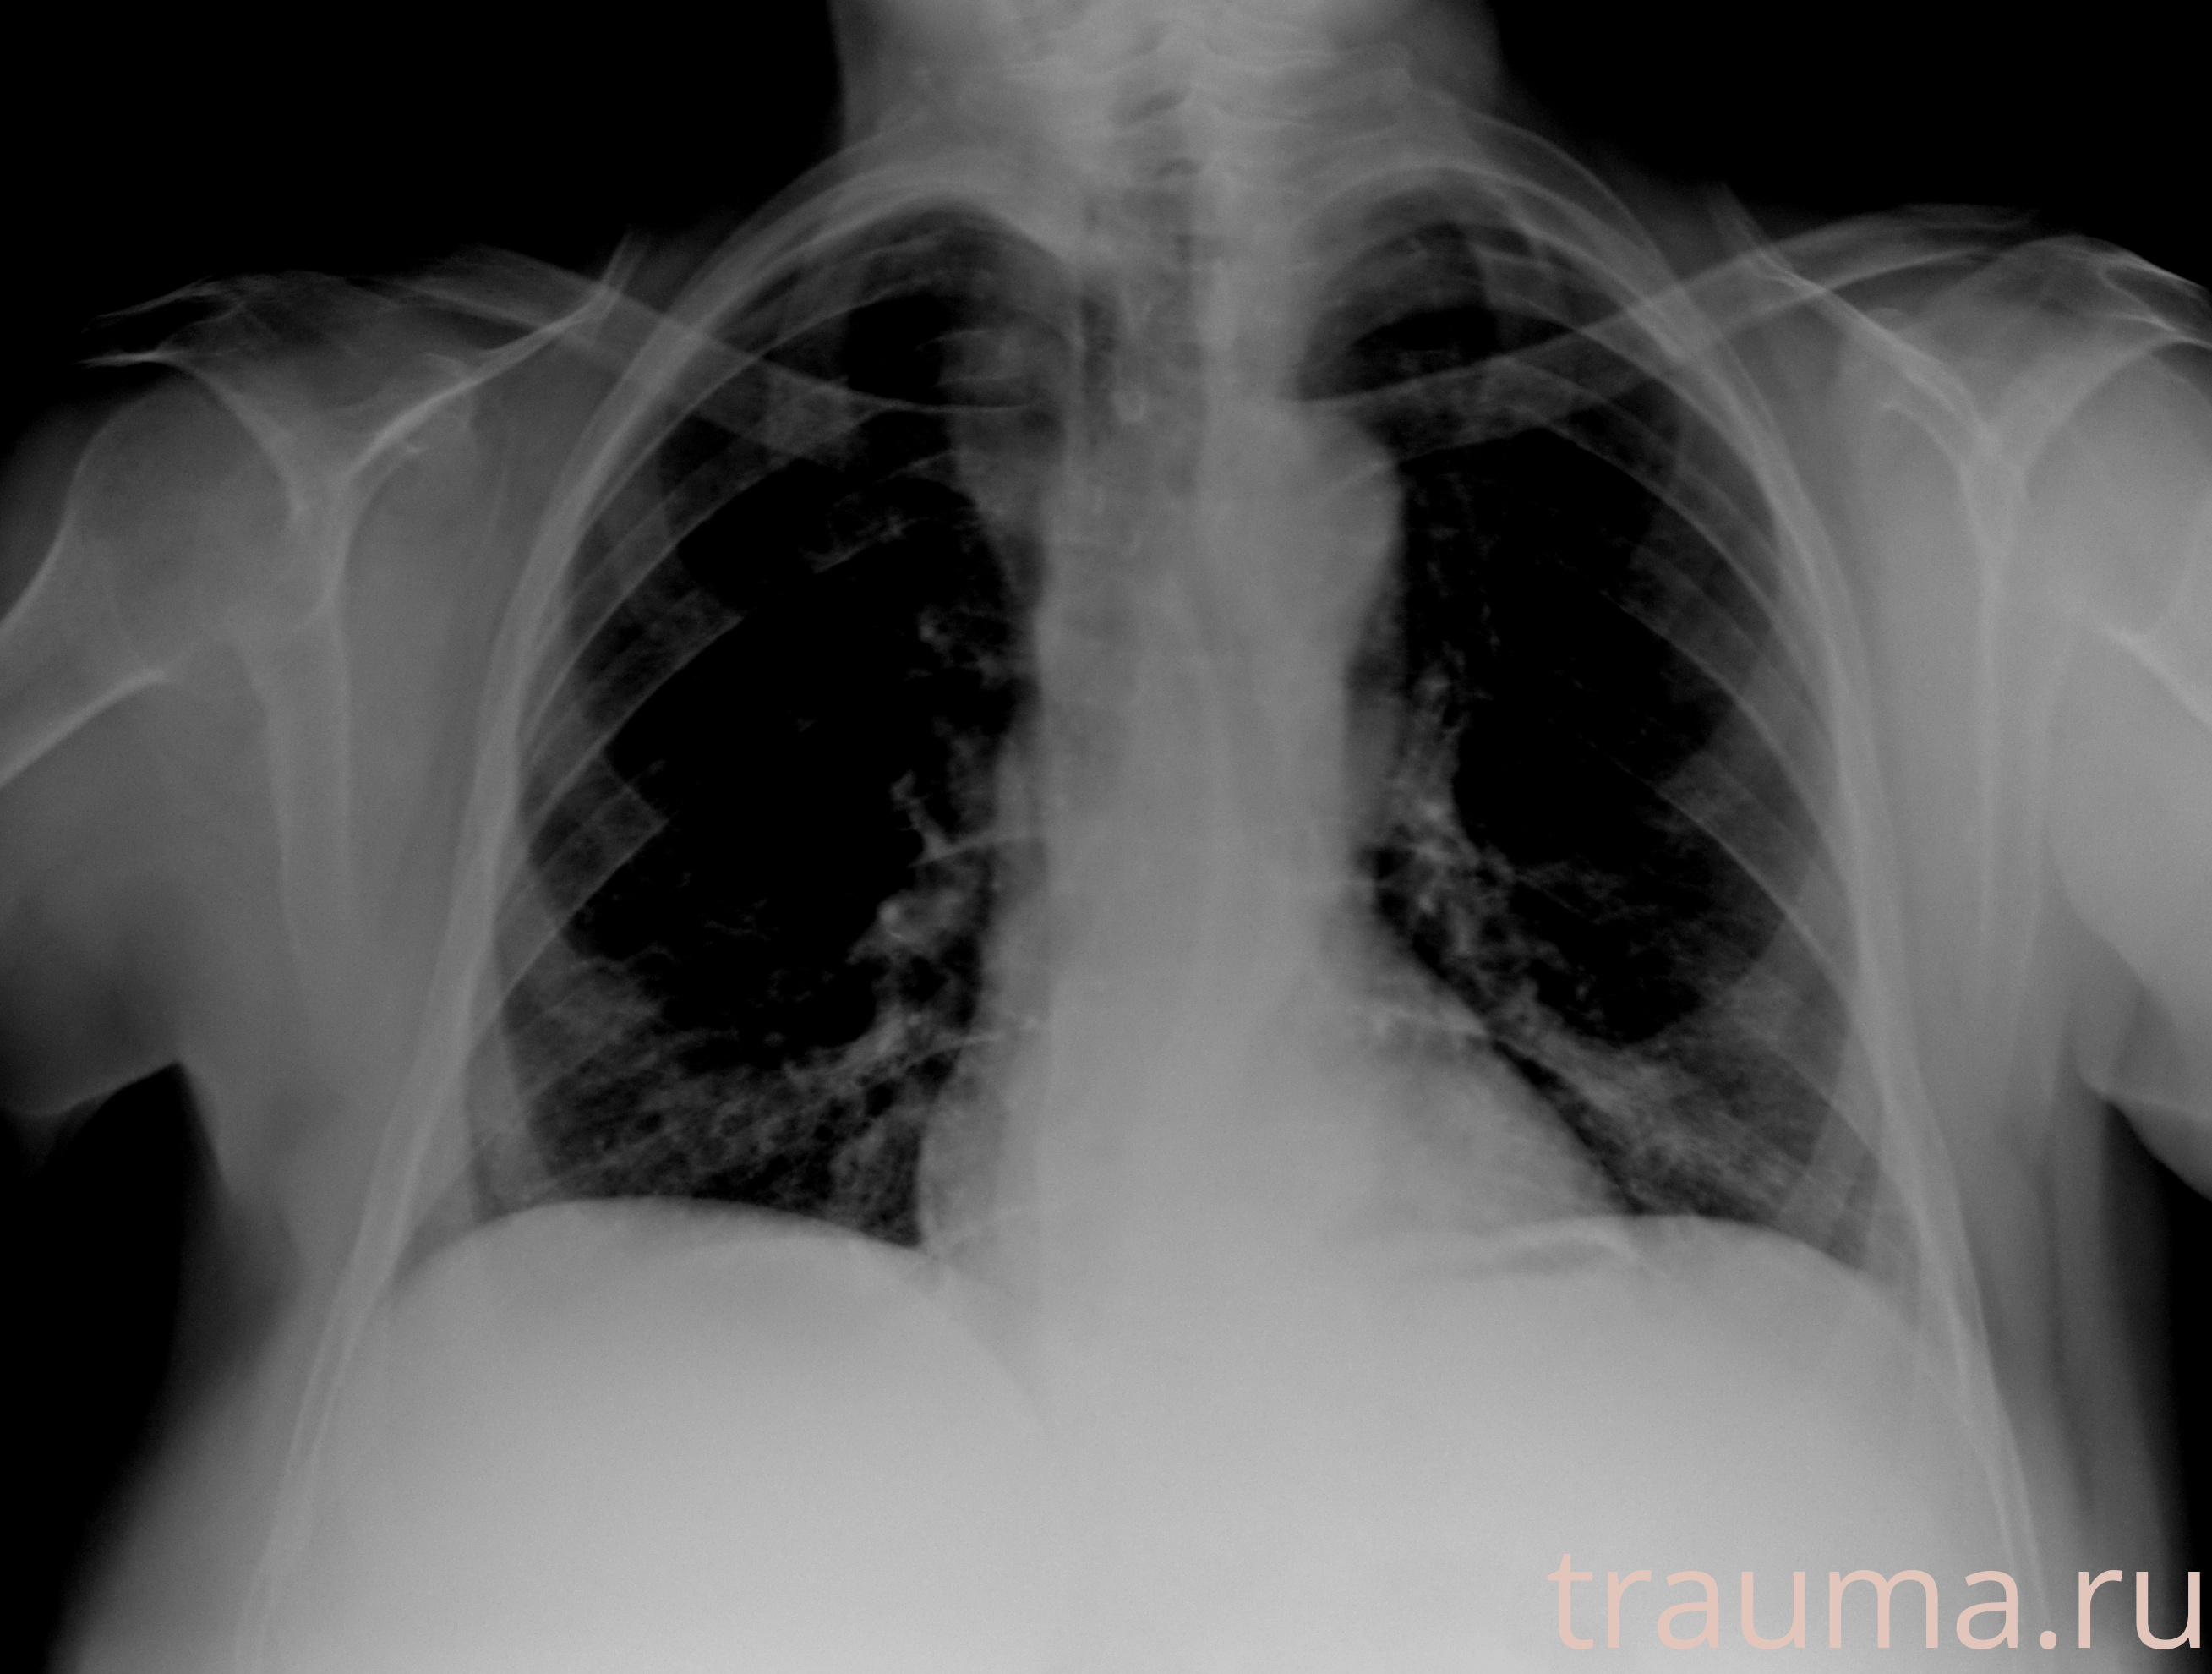

Рентген на дому: по вашему адресу приезжает врач-рентгенолог, травматолог-ортопед с мобильным рентгеновским аппаратом, проводит диагностику травмы или заболевания, делает необходимые рентгенограммы, дает рекомендации по дальнейшему лечению. Получить качественные снимки в домашних условиях возможно благодаря уникальной методике, разработанной МосРентген Центром для института  Склифосовского